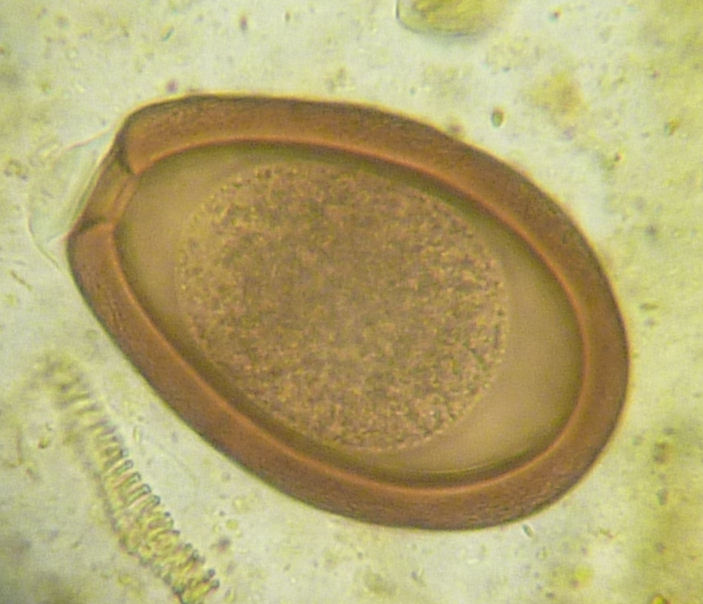

Fecal Exams

images/Nematode.jpg

images/coccidia.jpg